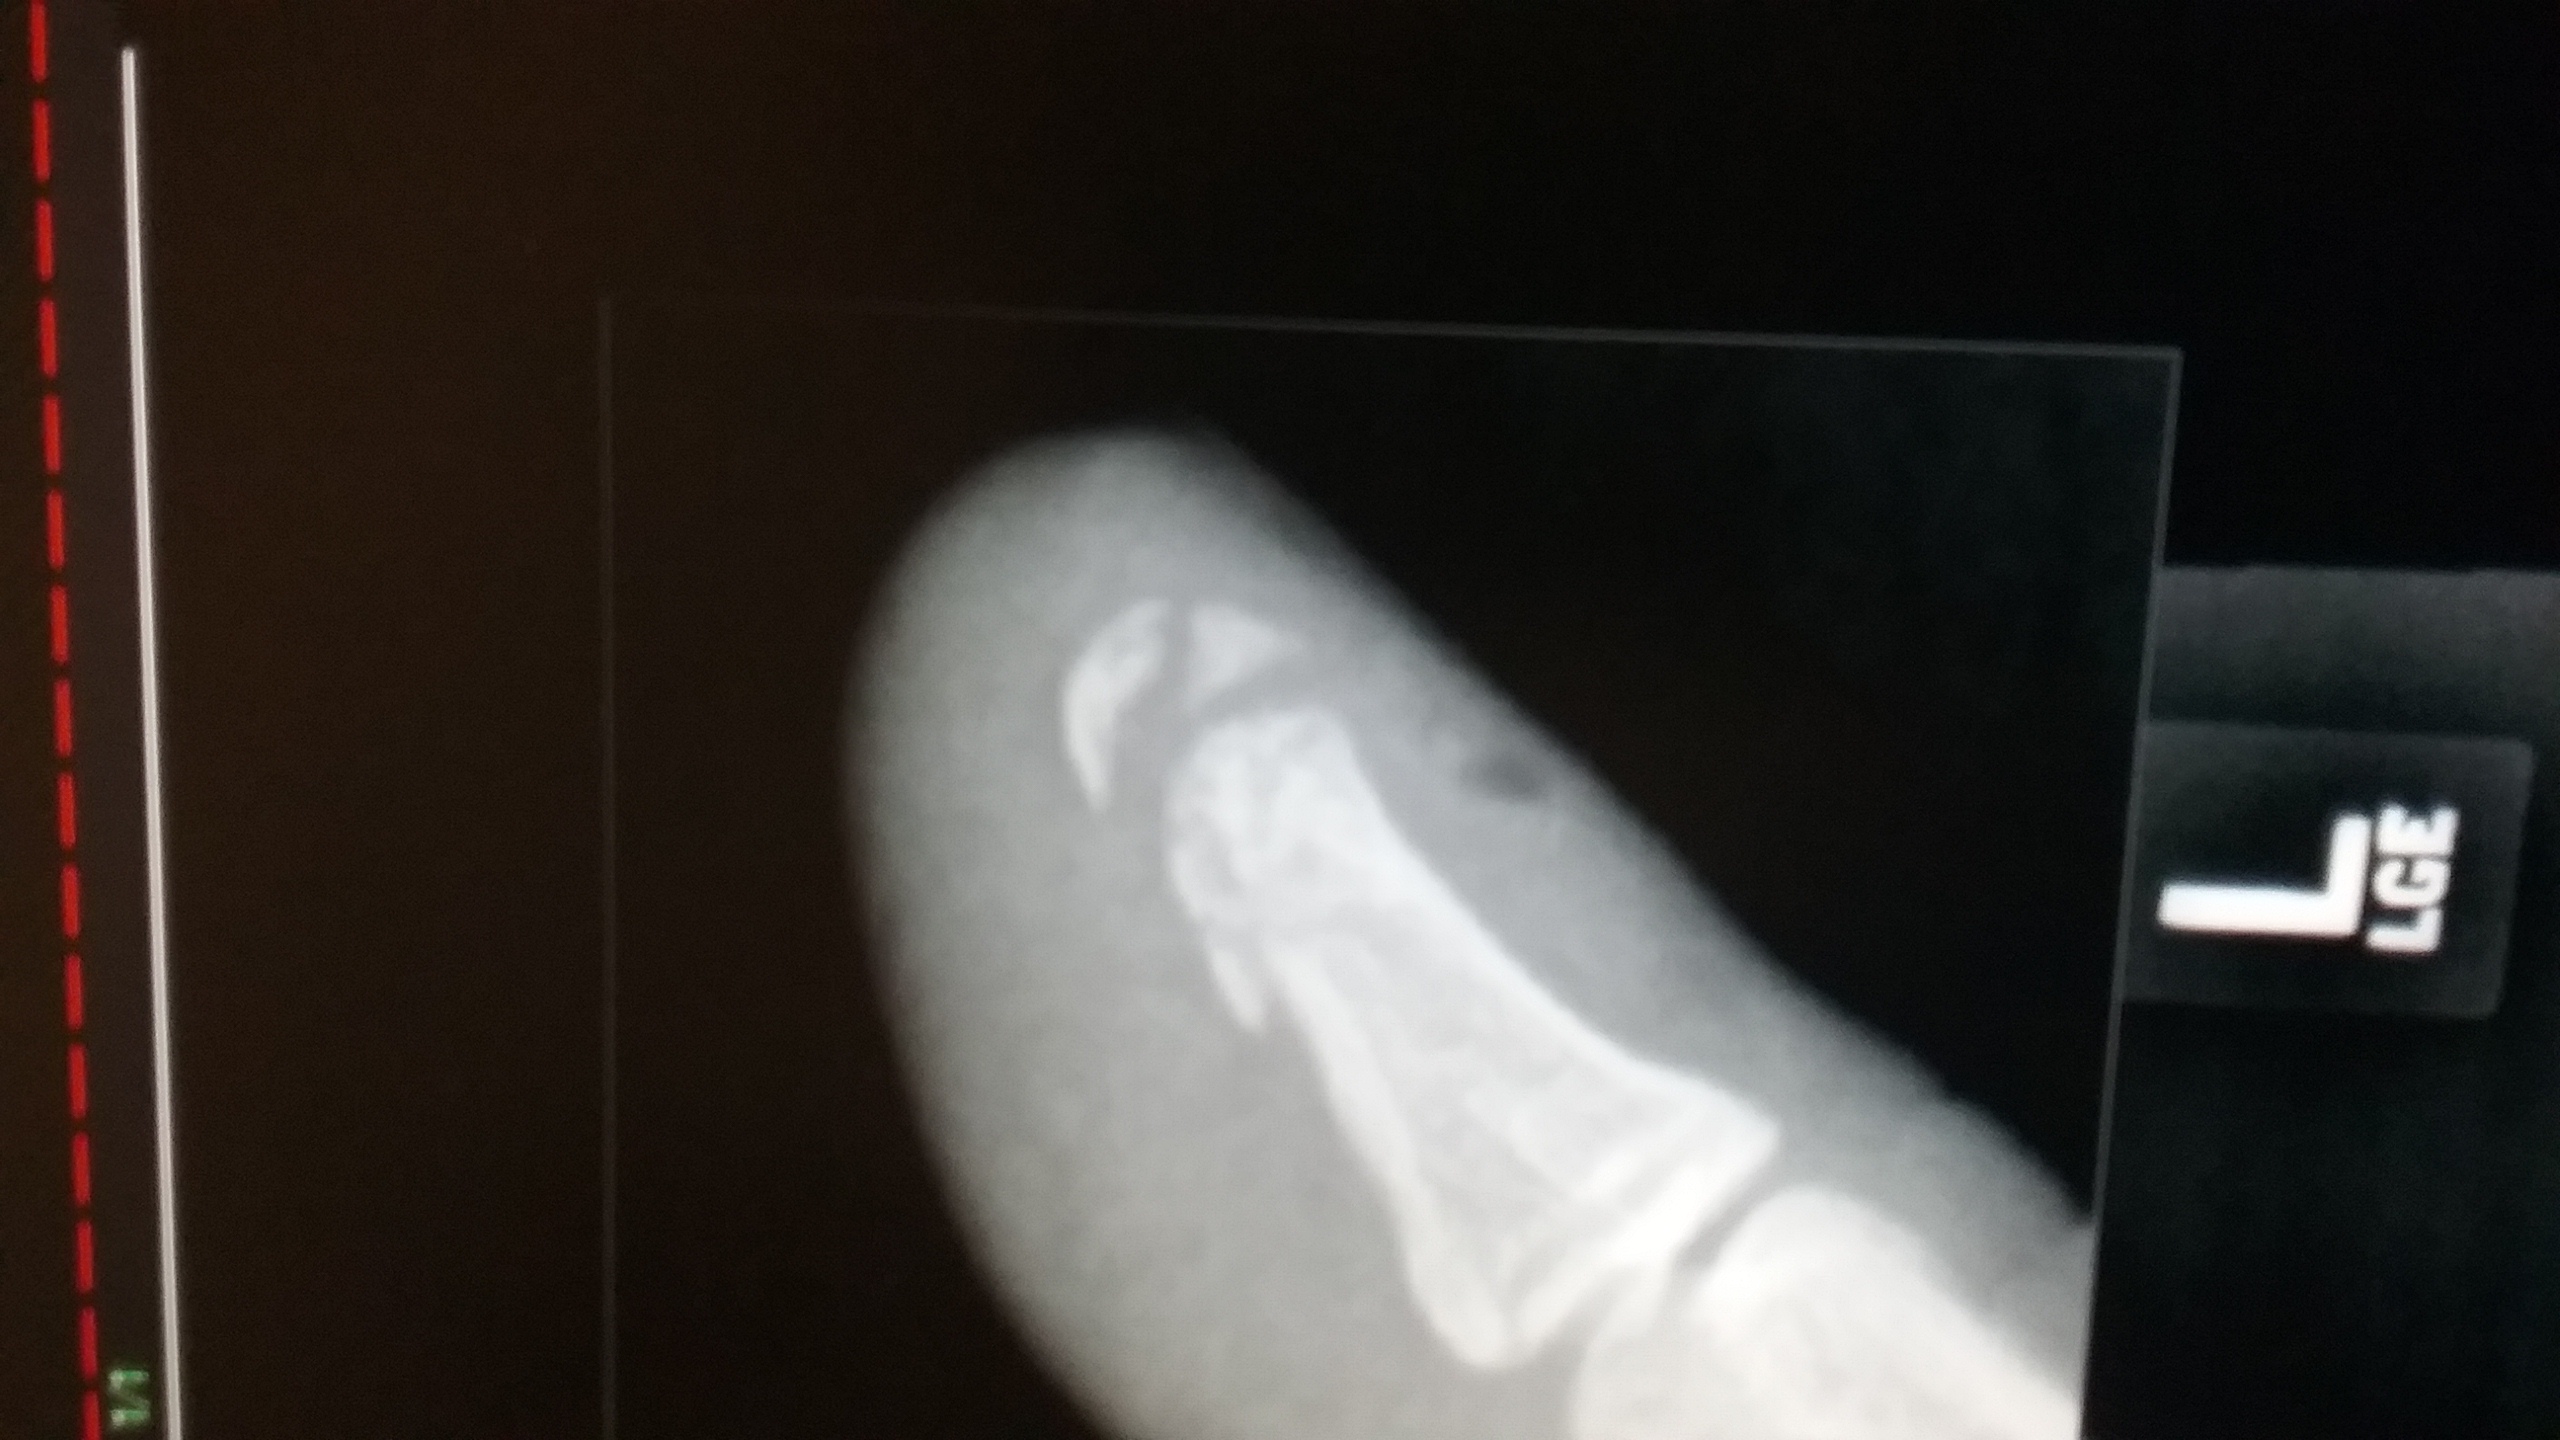

The thumb wasn't healing very quickly and i keep aggrivating it. So i had some x rays done....4 chunks of bone in the tip of my thumb. 1489797037768.jpg

Saw the ortho doc today. The pain is minimal...unless i bump it. Basically the pieces stay in and it heals slowly over time. Several weeks to several months. The key is avoiding re injury and avoiding infection. The hole in the nail from puncturing it can be an infection point. So when you puncture the nail be sure to serilize the needle and the finger to be punctured.